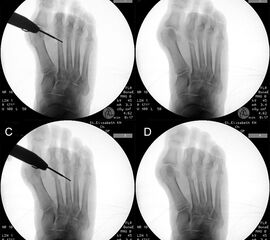

Zum Lesen der Bildbeschreibung und zur Vollansicht bitte das Bild anklicken.

Zum Lesen der Bildbeschreibung und zur Vollansicht bitte die Bilder anklicken.